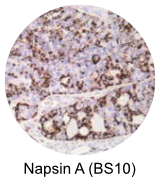

| Napsin A - Clone BS10 Napsin is a pepsin-like aspartic proteinase, in the A1 group of the AA class of proteinases. There are two closely related napsins, napsin A and napsin B. Napsin A is expressed as a single chain protein with the molecular weight of approximately 38 kDa. Napsin A is expressed in type II pneumocytes and in adenocarcinomas of lung. The high specificity expression of napsin A in adenocarcinomas of lung is useful to distinguish primary lung adenocarcinomas from adenocarcinomas of other organs. View Product Data Sheet |